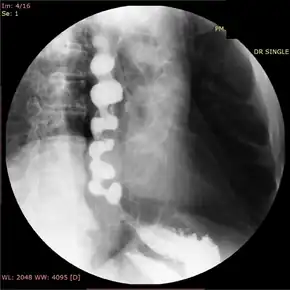

In people who have dysphagia, testing may first be done to exclude an anatomical cause of dysphagia, such as distortion of the anatomy of the esophagus. This usually includes visualization of the esophagus with an endoscope, and can also include barium swallow X-rays of the esophagus. Endoscopy is typically normal in patients with nutcracker esophagus; however, abnormalities associated with gastroesophageal reflux disease, or GERD, which associates with nutcracker esophagus, may be seen.[16] Barium swallow in nutcracker esophagus is also typically normal,[6] but may provide a definitive diagnosis if contrast is given in tablet or granule form. Studies on endoscopic ultrasound show slight trends toward thickening of the muscularis propria of the esophagus in nutcracker esophagus, but this is not useful in making the diagnosis.[17]